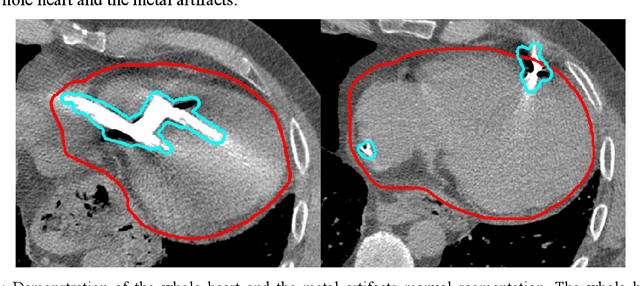

Abstract:Background: Quantification of cardiac motion on pre-treatment CT imaging for stereotactic arrhythmia radiotherapy patients is difficult due to the presence of image artifacts caused by metal leads of implantable cardioverter-defibrillators (ICDs). New methods are needed to accurately reduce the metal artifacts in already reconstructed CTs to recover the otherwise lost anatomical information. Purpose: To develop a methodology to automatically detect metal artifacts in cardiac CT scans and inpaint the affected volume with anatomically consistent structures and values. Methods: ECG-gated 4DCT scans of 12 patients who underwent cardiac radiation therapy for treating ventricular tachycardia were collected. The metal artifacts in the images were manually contoured. A 2D U-Net deep learning (DL) model was developed to segment the metal artifacts. A dataset of synthetic CTs was prepared by adding metal artifacts from the patient images to artifact-free CTs. A 3D image inpainting DL model was trained to refill the metal artifact portion in the synthetic images with realistic values. The inpainting model was evaluated by analyzing the automated segmentation results of the four heart chambers on the synthetic dataset. Additionally, the raw cardiac patient cases were qualitatively inspected. Results: The artifact detection model produced a Dice score of 0.958 +- 0.008. The inpainting model was able to recreate images with a structural similarity index of 0.988 +- 0.012. With the chamber segmentations improved surface Dice scores from 0.684 +- 0.247 to 0.964 +- 0.067 and the Hausdorff distance reduced from 3.4 +- 3.9 mm to 0.7 +- 0.7 mm. The inpainting model's use on cardiac patient CTs was visually inspected and the artifact-inpainted images were visually plausible. Conclusion: We successfully developed two deep models to detect and inpaint metal artifacts in cardiac CT images.